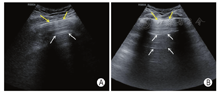

应观察是否存在胸膜线异常(光滑、连续性)、B线(数目及分布)、实变(范围、支气管充气征)、胸腔积液(性质)、气胸等。B线、肺泡间质综合征与白肺(图7)三种声像图表现反映肺内含水量由轻到重的程度。

肺泡间质综合征:当任一扫描区域内有连续两个以上肋间隙存在融合B线时。

白肺:如果两侧肺的每个扫描区域均表现为致密B线即为白肺。

肺实变:肺组织完全失气化后表现为实性组织回声,呈大小不等的斑片状或者"肝样变",可伴有"支气管充气征"或者"支气管充液征"(图9)。

胸腔积液:超声表现为胸膜腔内低/无回声区,可见条索样分隔,脓胸时应注意与实变的肺组织鉴别(图10)。